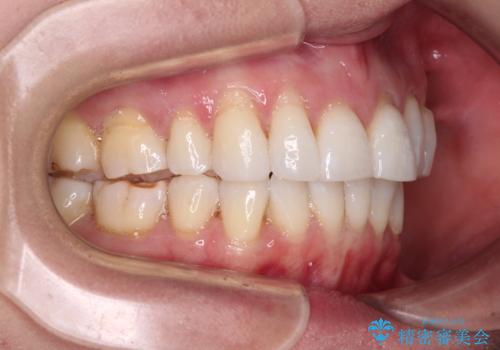

後戻りで突出した口元を引っ込めたい インビザライン矯正治療

- 上の前歯の出っ歯を治したいとのことで来院された患者様です。

後戻りによる再矯正というもともあり、インビザラインを希望されていました。

上顎の歯は後方移動とIPR(歯と歯の間を削る)によって口元が引っ込むように、下顎は歯列全体の拡大とIPRによって上顎とバランスよく咬み合うように設計し、インビザラインにより治療を行うこととしました。

治療を開始して暫くして、勤務先から2年以上帰国することができず、それまでの移動がほとんど後戻りしてしまい、帰国後に再度後戻りをリカバリーするための治療を行うこととなりました。

5年以上の治療期間がかかりましたが、気になっている部分を改善することができました。